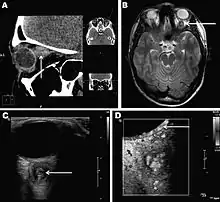

Infections in humans[3] usually manifest as a single subcutaneous nodule, which is caused by a macrofilaria that is trapped by the immune system. Subcutaneous migration of the worm may result in local swellings with changing localization. In addition, rare cases of organ manifestation have been reported, affecting the lung, male genitals, female breast, or the eye. The latter is found in particular during the migratory phase of the parasite. D. repens occurs more commonly in adults (aged 40–49 years). The only exception is in Sri Lanka, where children younger than nine years are most likely to be infected. The youngest individual reported was aged four months.[4]

Final diagnosis is established by microscopic examination of the excised worm. Making a definite species diagnosis on morphologic grounds is difficult, because a large number of zoonotic Dirofilaria species have been described that share morphologic features with D. repens.

Antifilarial medication for infected humans generally is not supported in the medical literature.[2] One group of authors has recommended a single dose of ivermectin followed by three doses of diethylcarbamazine if the syndrome is recognized prior to surgery. However, most cases are diagnosed retrospectively, when histopathological sections of biopsy or excision material are viewed. In terms of surgical care, excision of lesions and affected areas is the treatment of choice for patients with human dirofilariasis. Some authors have recommended a period of observing chest coin lesions for several months if dirofilariasis is suspected and no other features in the history or examination suggesting malignancy or other infection are present. Also, no specific diet is recommended for patients with dirofilariasis.